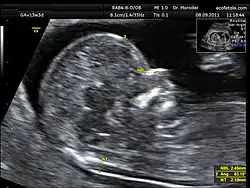

Przezierność fałdu karkowego (ang. nuchal translucency, NT) – parametr oceniany w badaniu USG płodu, odzwierciedlający obrzęk tkanki podskórnej w okolicy karkowej; jest to odległość między tkanką podskórną a skórą na wysokości karku płodu. Zwiększenie wartości NT występuje w niektórych zespołach spowodowanych aberracjami chromosomalnymi: zespole Downa, zespole Edwardsa, a zwłaszcza w zespole Turnera.

Pomiar NT jest najbardziej miarodajny między 11. a 14. tygodniem ciąży. Norma NT, określona dla danej populacji, obejmuje wartości do 95 percentyla i jest uzależniona od wymiaru ciemieniowo-siedzeniowego (CRL); w praktyce NT nie powinno przekraczać 2,5 mm. NT jest wprost proporcjonalne do ryzyka wystąpienia trisomii u płodu:

Według Nicolaidesa pomiar należy wykonywać z uwzględnieniem poniższych zaleceń:

- CRL powinien wynosić 45–84 mm

- optymalny wiek ciążowy do wykonania badania to 11-13+6 tygodni.

- istotne jest uzyskanie dobrego obrazu strzałkowego płodu

- płód powinien zajmować 3/4 pola, odległość między znacznikami powinna być jak najmniejsza i nie przekraczać 0,1 mm

- należy rozróżnić skórę płodu i owodnię

- największy wymiar NT (między skórą a miękkimi tkankami nad kręgosłupem szyjnym) powinien być zmierzony kilkakrotnie, a obraz z USG powinno się zarchiwizować

- płód powinien znajdować się w swobodnym ułożeniu, przygięciowe lub odgięciowe ułożenie główki może fałszować wynik badania